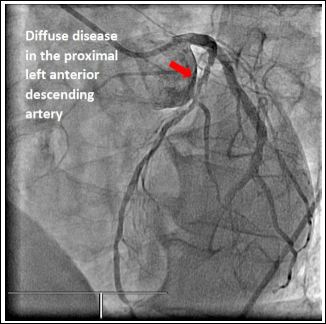

Our first case was a 57-year-old male with a history of moderately severe aortic stenosis presenting with syncope and reduced effort tolerance. Preaortic valve replacement surgery, he had a diagnostic coronary angiogram which revealed an anomalous origin of his right coronary artery from the distal left circumflex artery and a significant left anterior descending artery lesion (Figure 1). The patient underwent successful bioprosthetic aortic valve replacement surgery with coronary artery bypass grafting of Left Anterior Descending artery (LAD).

Figure 1: Anomalous Origin of the Right Coronary Artery from the Distal Circumflex Artery.